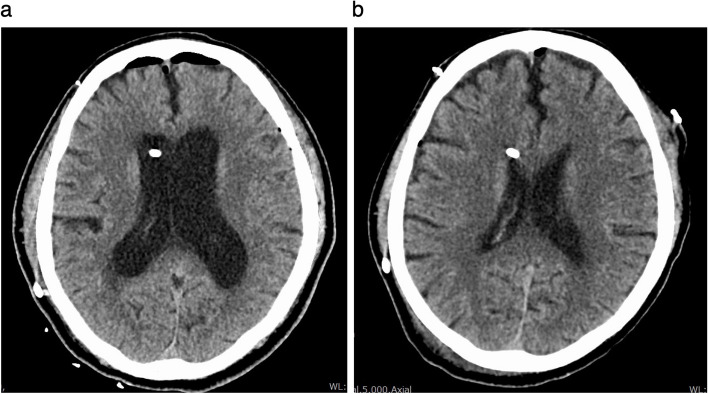

Case presentation: A 75-year-old male with a history of VP shunt for a fourth ventricle obstruction underwent cerebral vascular anastomosis in the prone position. His preoperative level of consciousness was clear. The surgery under general anesthesia was completed without any particular issues. After discontinuation of anesthesia, the patient did not awaken for over an hour. Postoperative CT revealed exacerbated hydrocephalus, likely from VP shunt occlusion. After pumping the reservoir of the VP shunt, the patient regained consciousness. He was extubated and discharged from ICU on the second postoperative day with no neurological issues.